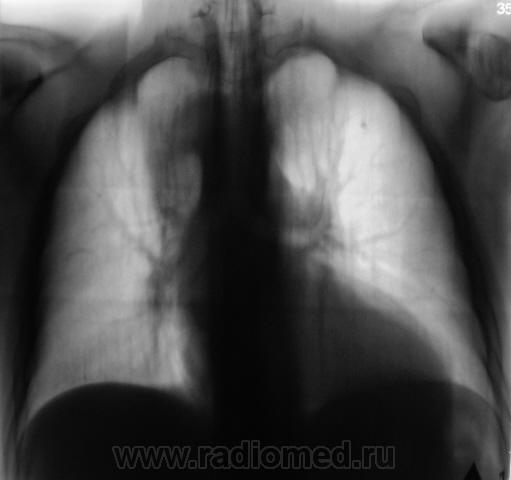

При расшифровке флюорограмм пациент взят на контроль. Жалоб не предъявляет.

Очень интересно! Третий раз подхожу к компу втечение дня... Овоидная тень с четкими ровными контурами, расположена субплеврально (или в средостении? Как будто трахею оттесняет), неоднородной структуры. В легочной ткани участок инфильтрации с мощной "дорожкой" к корню. Пожалуй, выскажусь за инфильтративный ТБС и туберкулому. А переломчик VII ребра слева похож на относительно свежий.

Считаю важным осмотр щитовидной железы на УЗИ и вилочковой, если возможно, вероятны их изменения, которые проявились на данной рентгенограмме. А в S2 слева единичный кальцинат. И консолидированный перелом 7 ребра слева по задней подмышечной линии.

Пожалуй процесс исходит из средостения и явно "злой"....

А может это праволежащая аорта?

Да, вроде как dextra-позиция аорты, под скопией бы глянуть.